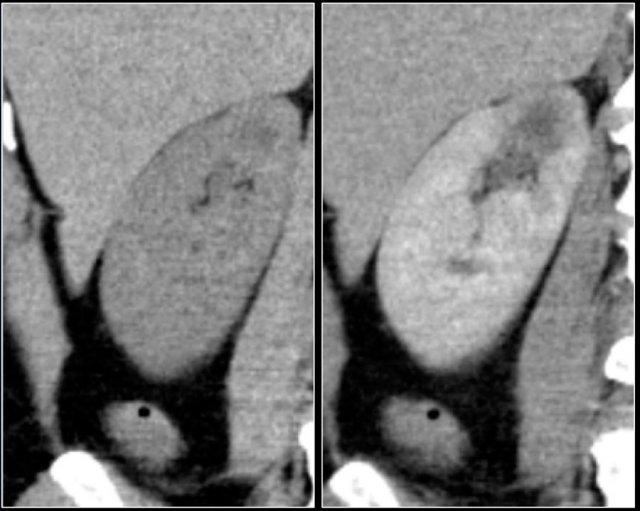

Tổn thương thâm nhiễm ở cực trên thận phải, hầu như không thấy trên ảnh không tiêm thuốc (bên trái), thấy rõ ràng ở thì thận (bên phải). Giải phẫu bệnh xác nhận RCC tế bào sáng

Trong số tất cả các RCC tế bào sáng, khoảng 5% có kiểu tăng trưởng thâm nhiễm.

Mặc dù đây chỉ là một tỷ lệ nhỏ trong số các RCC, nhưng tần suất chung của RCC khiến đây trở thành một chẩn đoán phân biệt quan trọng đối với tổn thương thâm nhiễm dạng hình đậu (bean-type).

RCC thâm nhiễm có tính chất xâm lấn cao và tăng sinh mạch máu.

Tổn thương làm thay đổi cấu trúc nội tại của thận nhưng vẫn bảo tồn đường bờ thận. Các bất thường hệ thống đài bể thận có thể tương tự như những gì thấy trong ung thư biểu mô tế bào chuyển tiếp (transitional cell carcinoma).